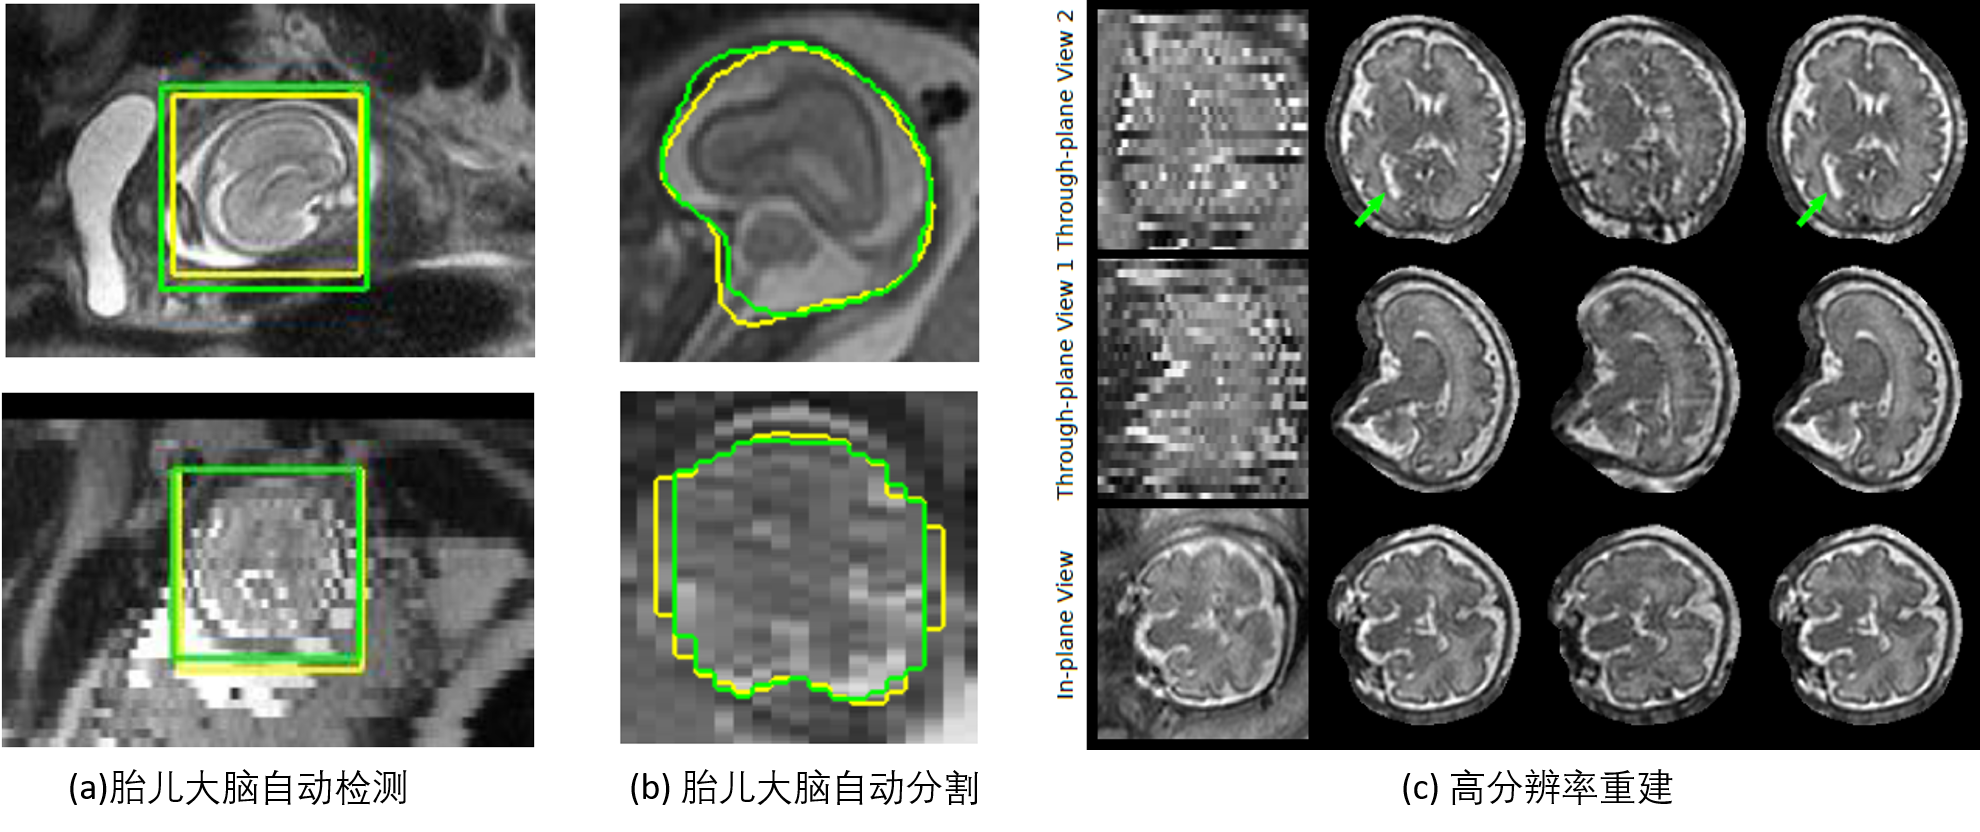

本项目中,我们提出了一个全新的系统,可以全自动地完成磁共振图像中胎儿大脑的定位、精确分割及高分辨率三维图像重建,这对于胎儿大脑发育的临床研究具有重要意义。本研究成果中的胎儿大脑自动定位、分割及高分辨率重建的相关代码已经在Github上开源,有望促进胎儿大脑磁共振图像相关领域的研究。该项成果已经被比利时鲁汶大学用于研究脊柱裂对胎儿大脑发育的影响。